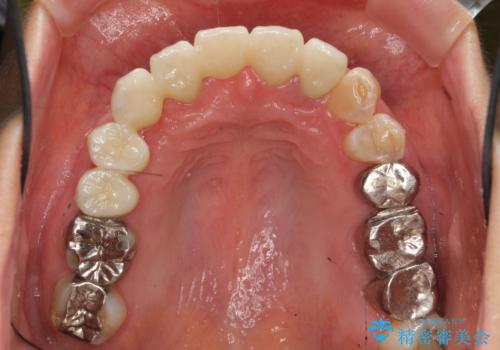

過度な咬合力 歯ぎしりで抜けた歯の欠損補綴

過度な力がかかり周囲の骨に高度な吸収が見られた犬歯は抜歯し、機能・審美性の回復をより咬合力に対して抵抗力のあるブリッジ補綴にて対応します。

- 56円(仮歯・フルジルコニアクラウン×7)費用は治療当時の料金となります

ブリッジによる欠損補綴を行ったのち、ナイトガードを夜間装着していただき歯を守ります。